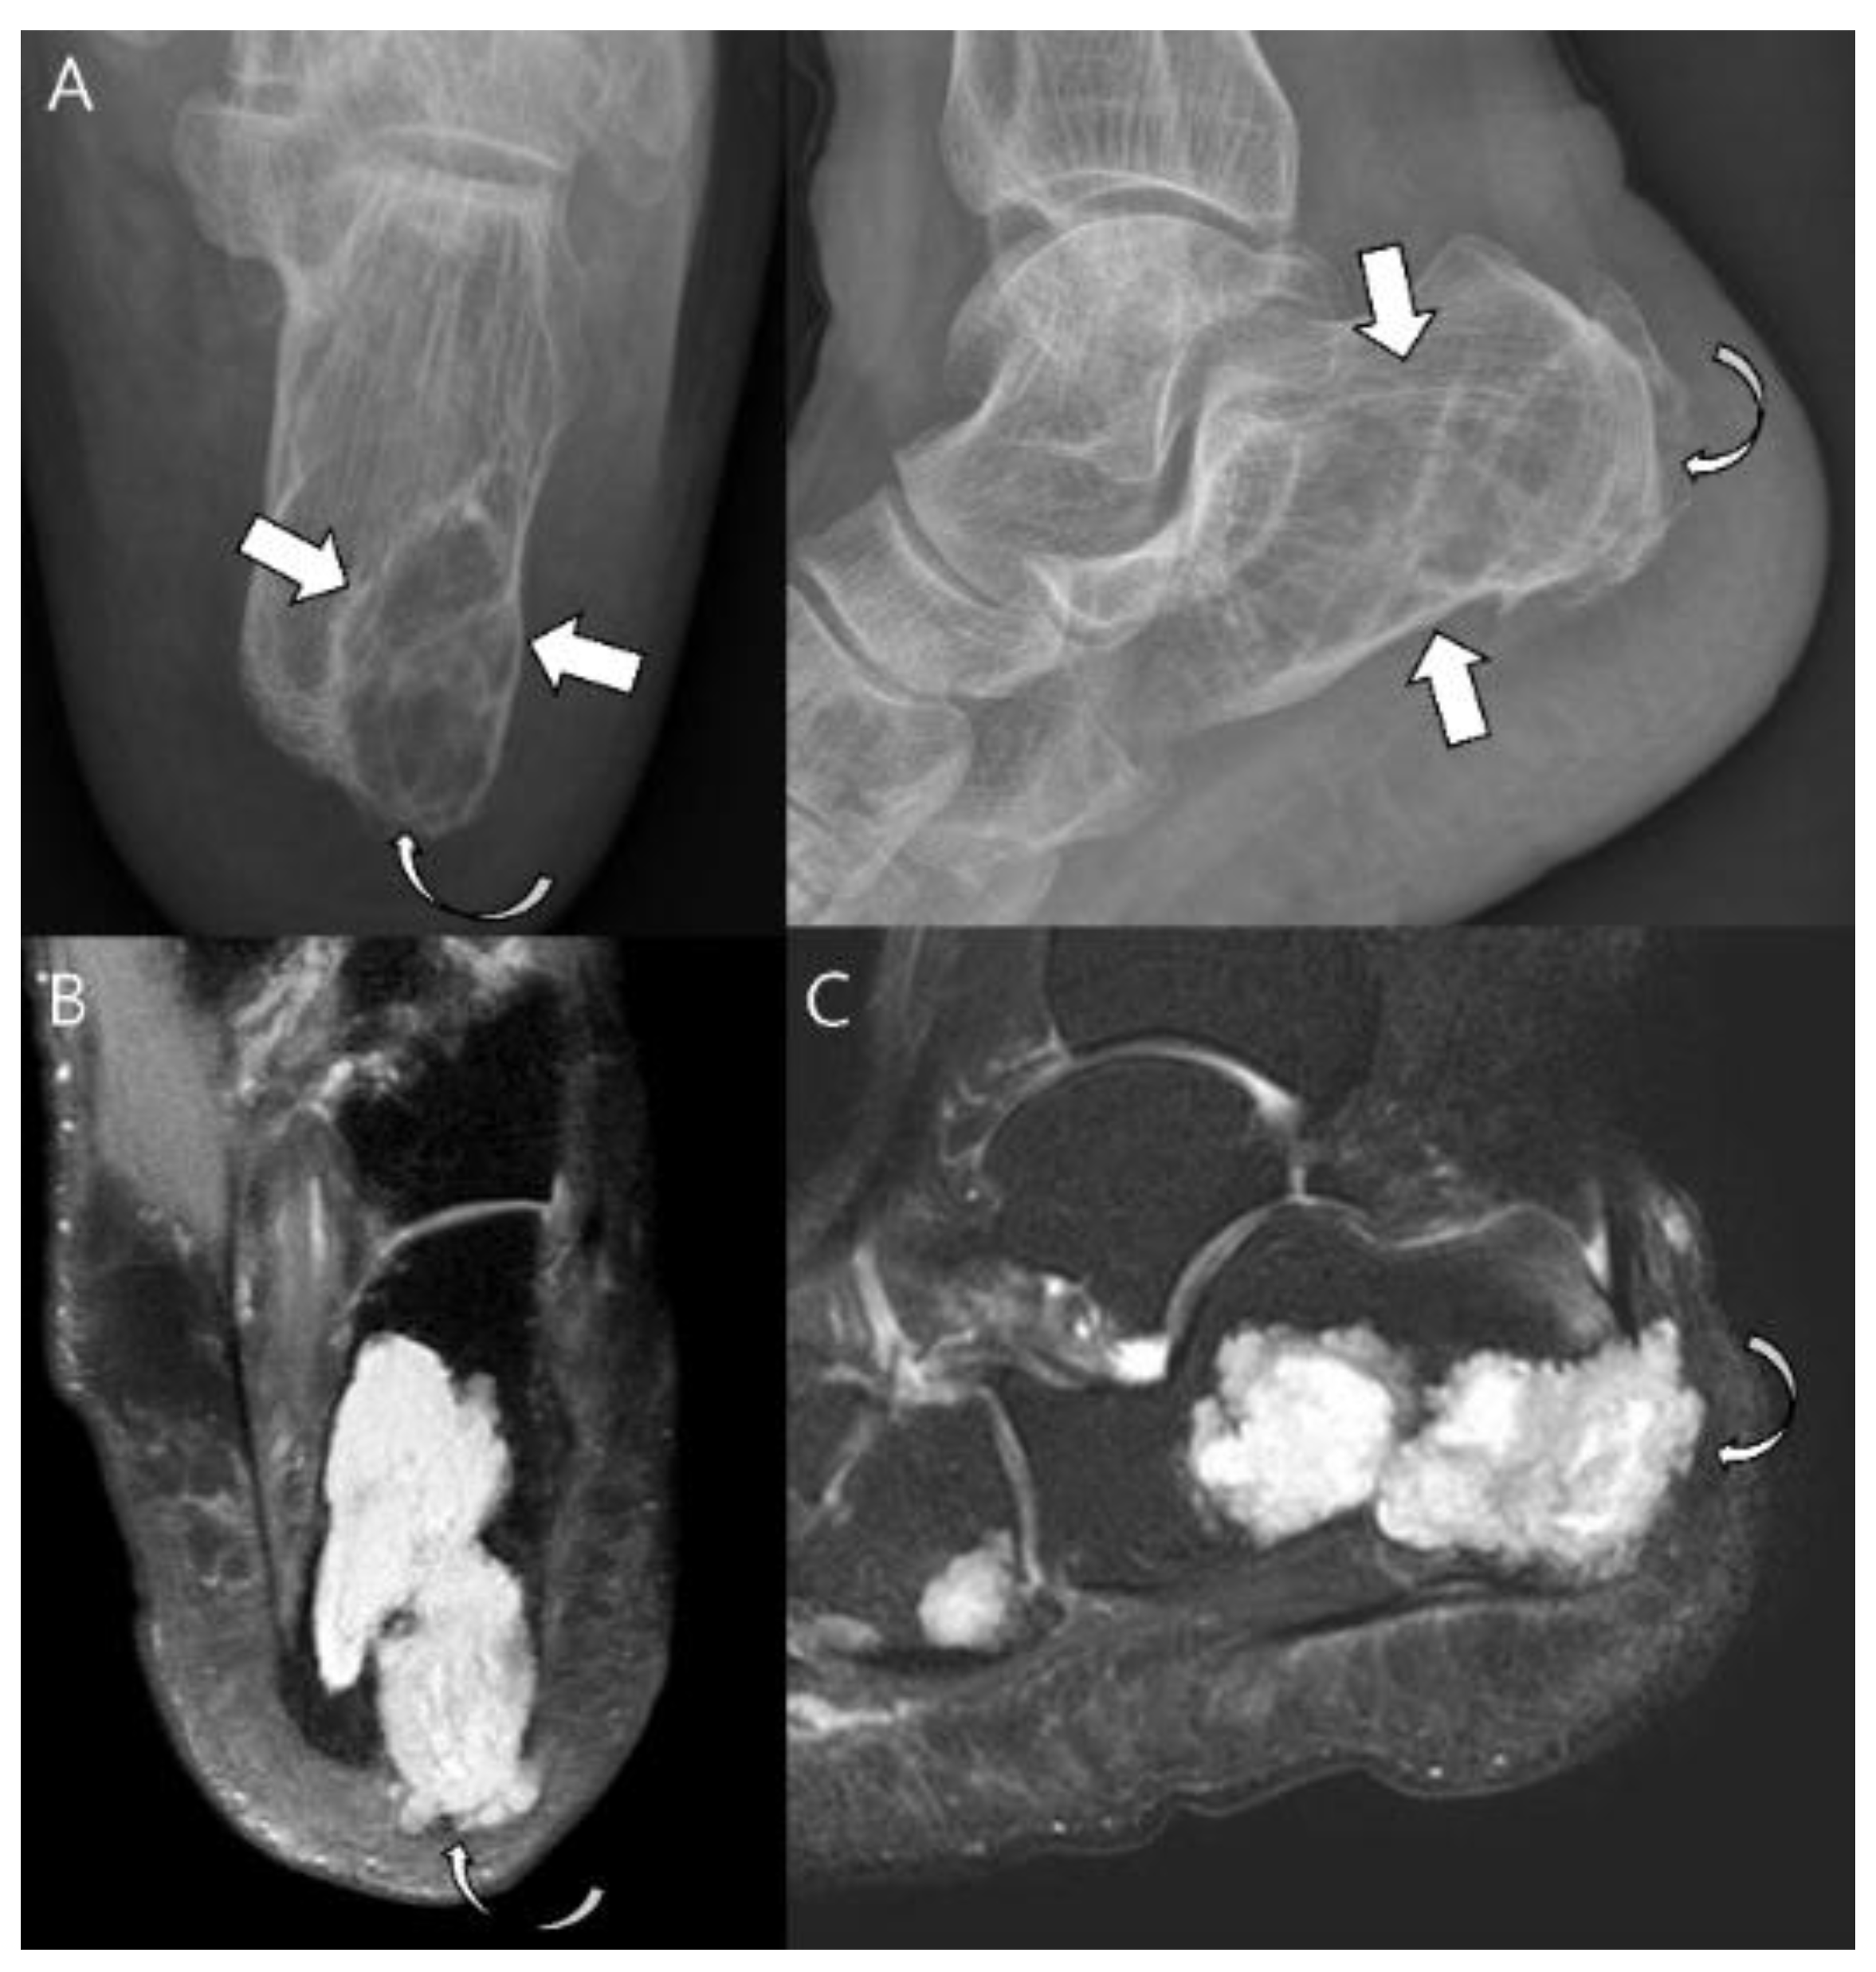

Cortical destruction and soft tissue masses are further findings that can indicate an aggressive process with a perfect specificity of 100% [8] (Figure 6). A more aggressive moth-eaten and permeative bone appearance with more ill-defined margins may be seen in higher-grade chondrosarcomas and is frequently associated with mesenchymal and dedifferentiated subtypes [1,18]. CT allows the optimal detection of matrix mineralization, particularly when it is subtle or in a complex anatomic area, in addition to the accurate evaluation of the length and depth of endosteal scalloping [1,15,24]. Cortical response or cortical destruction with extraosseous soft tissue extension can also be well visualized by CT [15,24,25]. The enhanced CT findings for chondrosarcoma include a mild peripheral rim and septal enhancement [1,24]. MRI is the best method for evaluating the extent of marrow replacement and soft tissue extension [1,24]. Conventional chondrosarcomas have water-rich hyaline cartilage, which presents as a bright signal surrounded by low-signal septa on T2-weighted images (T2WI) [15]. Areas of matrix mineralization have a low signal in all MR pulse sequences [15]. This feature often creates marked heterogeneity in T2WI [1]. On T1-weighted images (T1WI), marrow-replacing lesions show a low-to-intermediate signal with possible entrapped areas of pre-existing fat marrow, presenting with high signal intensity on T1WI [1]. Soft tissue extension is well demonstrated on MRI and the characteristics of soft tissue extension are identical to those of the intraosseous component [1,24]. The contrast enhancement pattern is typically mild in degree and peripheral and septal in pattern [1]. Higher-grade lesions appear, with larger soft tissue masses showing more prominent diffuse or nodular contrast enhancement [1]. Higher-grade conventional chondrosarcomas occur more frequently in the axial skeleton. The prevalence of CS2 and CS3 in the iliac bone is 70%, with a predilection for the area around the previous region of the triradiate cartilage (Figure 7). For comparison, the prevalence of CS2 and CS3 in the entire femur is 45% [20].

Figure 6.

Atypical cartilaginous tumor of the calcaneus in a 74-year-old woman. (A) Plain radiographs reveal a lytic lesion in the calcaneus (arrows) with a partially destructed cortex (curved arrow). (B) Axial and (C) sagittal T2-weighted images with fat suppression show a lesion with marked high-signal intensity with focal extraosseous soft tissue extension (curved arrows).